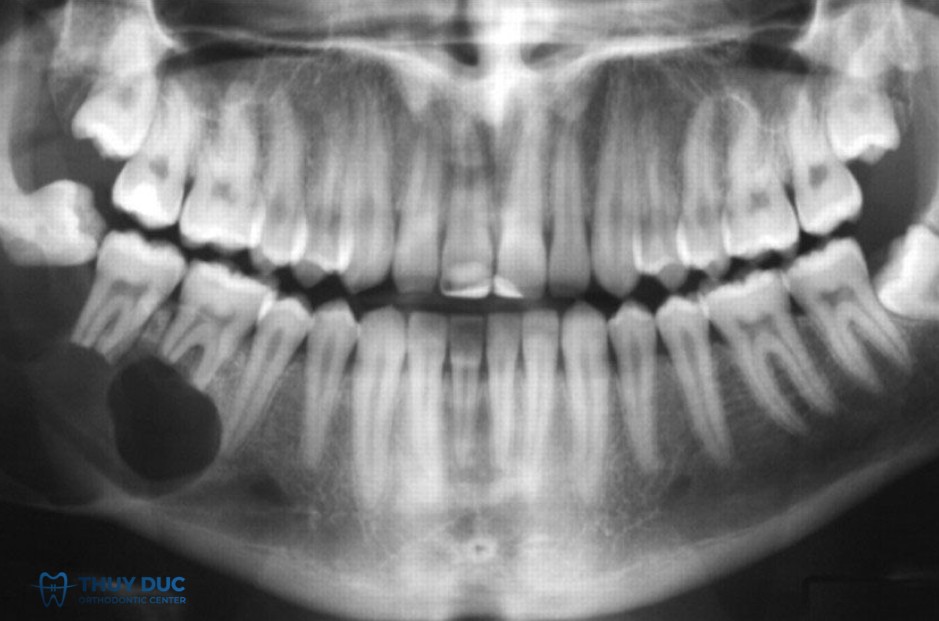

Phần lớn các trường hợp được phát hiện tình cờ trên phim X-quang, khi bệnh nhân đi khám vì một vấn đề răng miệng khác, hoặc trong các tình huống chẩn đoán hình ảnh thường quy như: chụp phim đánh giá răng sâu, viêm quanh chóp, kiểm tra trước chỉnh nha, lập kế hoạch nhổ răng khôn, hoặc khảo sát xương hàm trước khi cấy ghép implant. Khi đó, bác sĩ mới nhận thấy hình ảnh chóp chân răng phình to, tròn, khác biệt so với hình dạng sinh lý thông thường.

Trên phim cận chóp hoặc cắn cánh, có thể nhận thấy:

- Chóp chân răng phình to, tròn hoặc dạng chùy.

- Mất dần hình dạng thuôn đều sinh lý của chân răng.

- Vùng chóp có thể trông như “củ hành” hoặc “chùy ngược”.